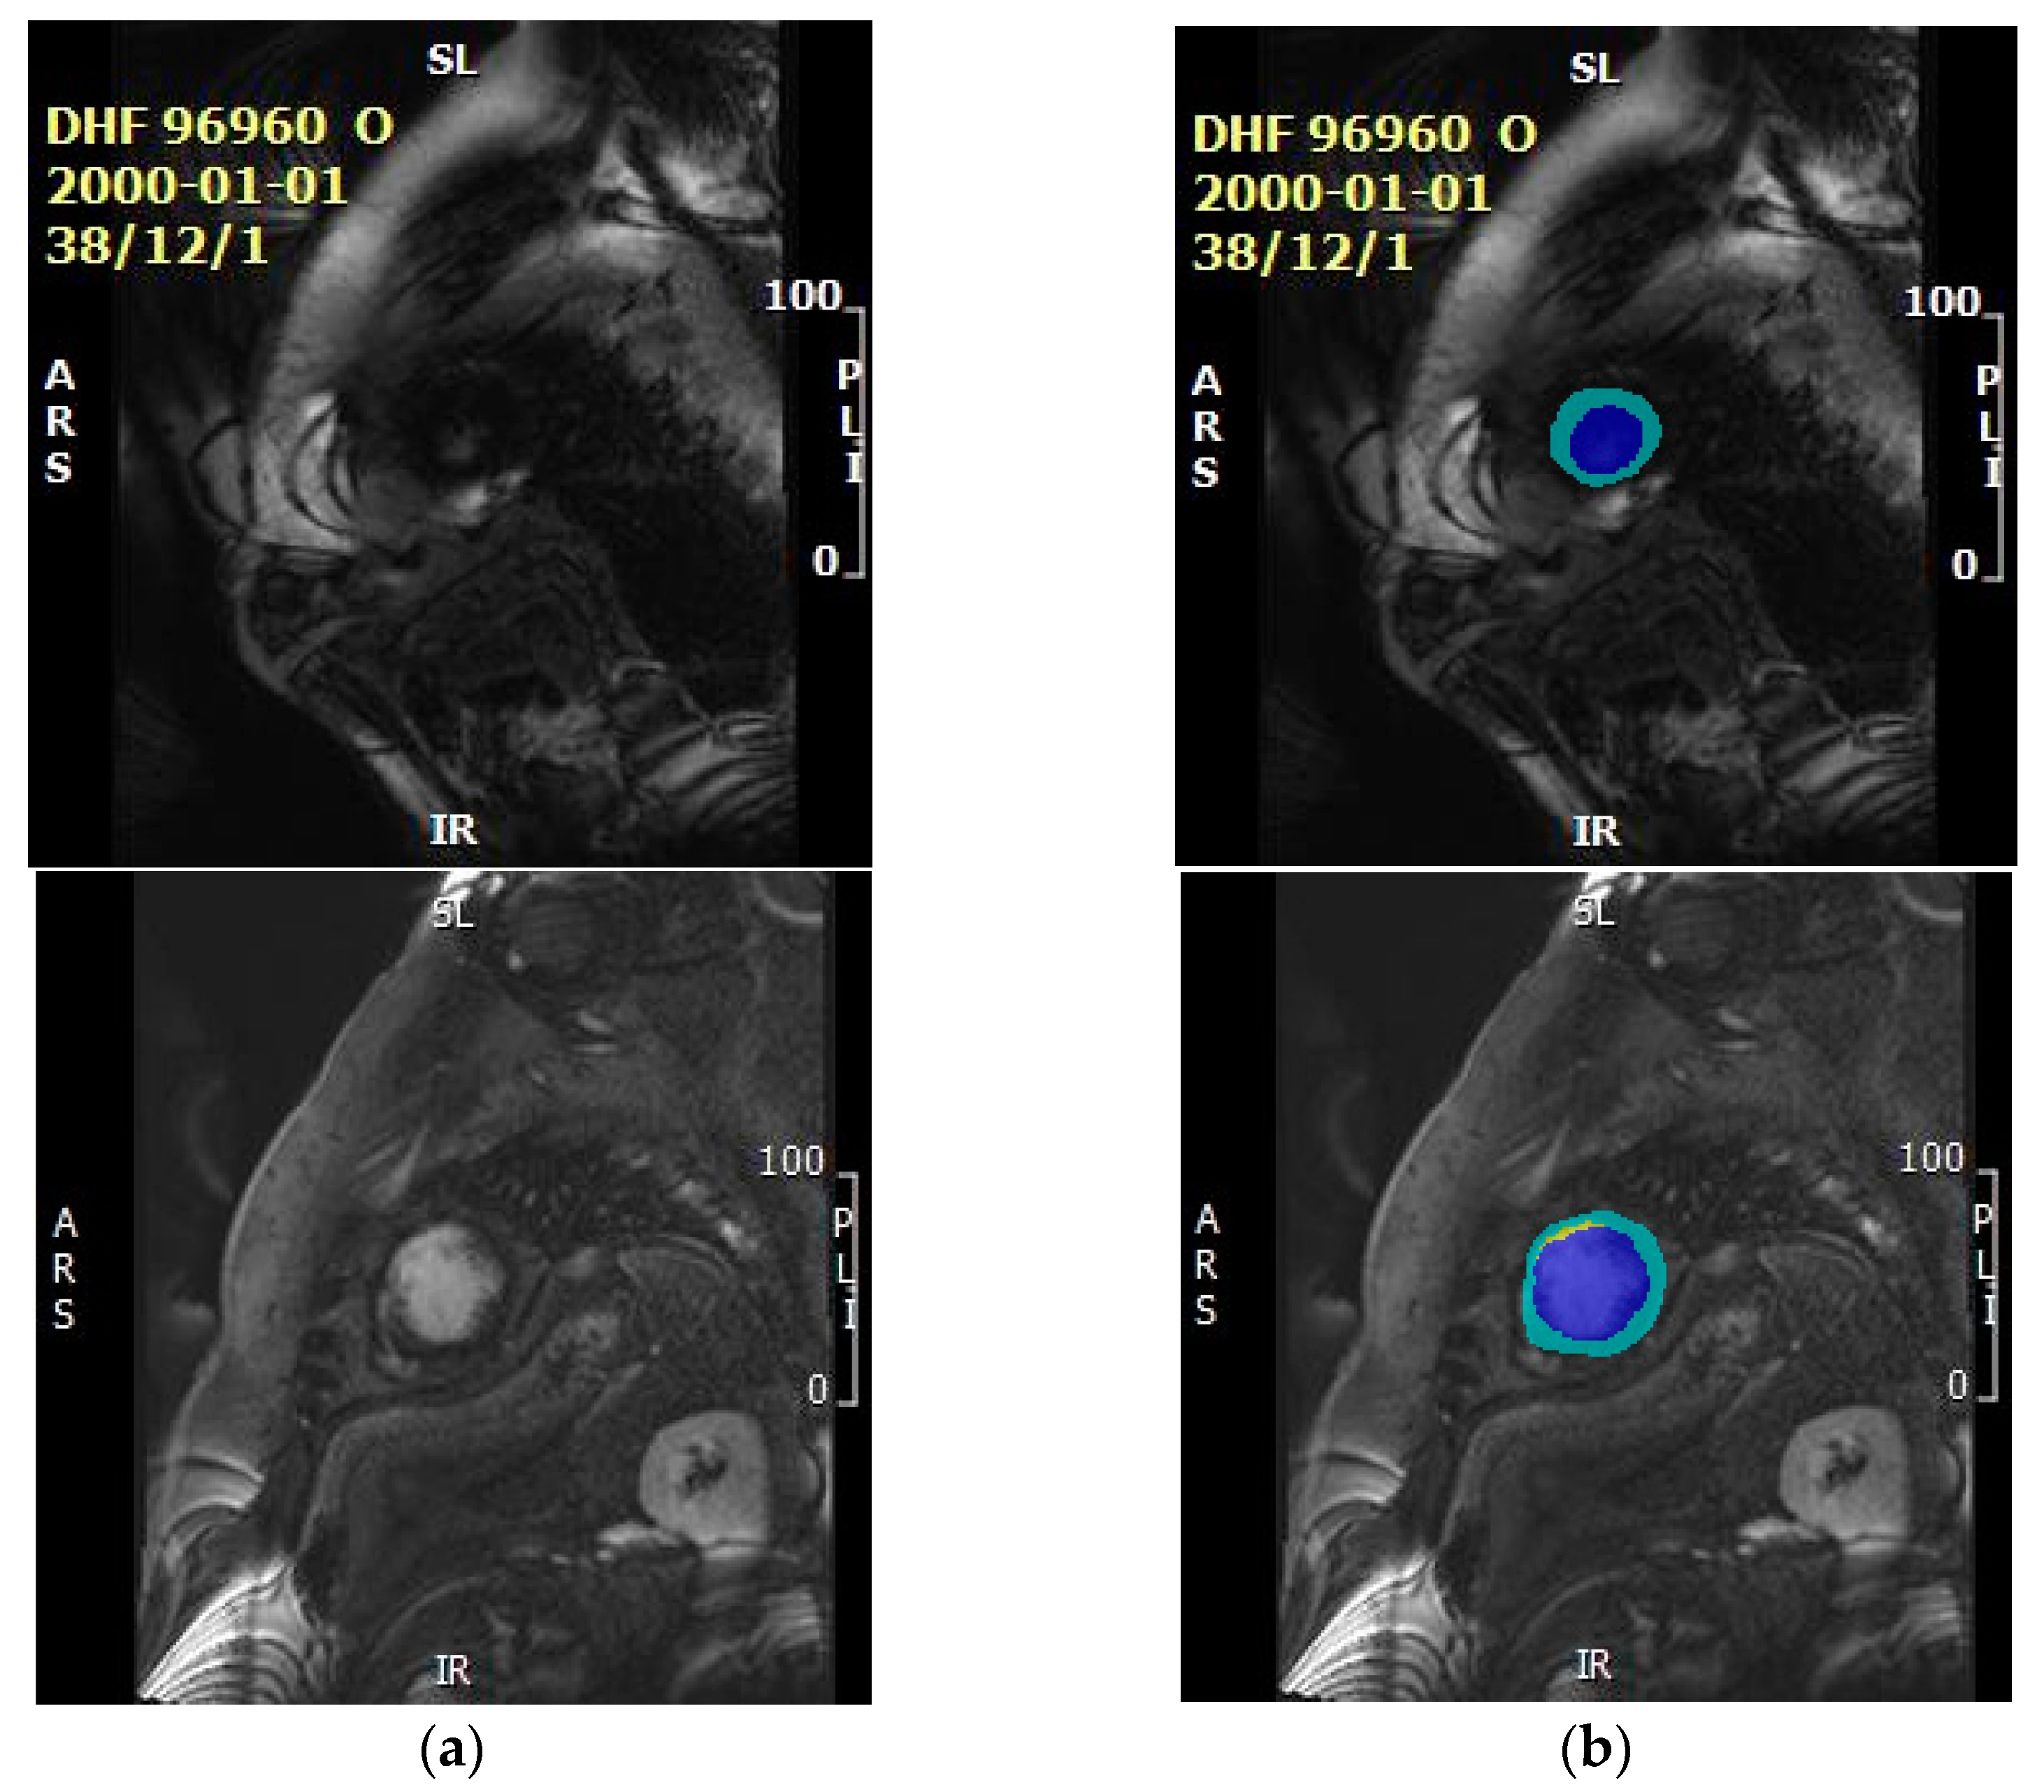

2. Materials

4.1. Data Preparation

4.3. Segmentation Result Based of Proposed Method